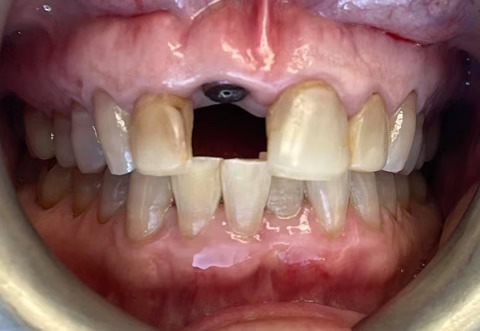

Case Study: Dental Implant

A patient with a missing tooth received a dental implant, restoring both function and aesthetics.